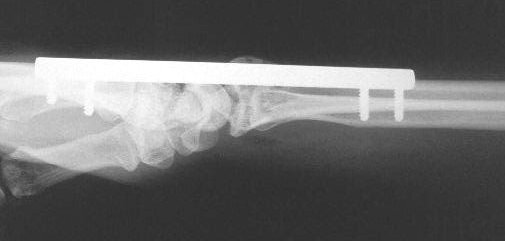

Clinical Example: Distraction plate fixation of distal radius fracture

distal radius fracture

distraction plate